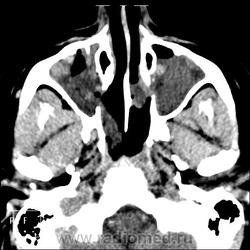

КТ ППН и носоглотки. Девушка 21 года. Полипозный риносинусит.

Госпитализирована для оперативного лечения. Удалены полипы носа. Вторым этапом планируется гайморотомия. Во время операции - подозрение на образование носоглотки. Сохраняется затруднение носового дыхания. Направлена на КТ. Категорически отказалась от контрастировния (лекарственная полиаллергия, боится).

Полип в носоглотке справа. Нарушена пневматизация придаточных пазух носа кроме левой решётчатой. В левой гайморовой на дне неясно что…

На дне гайморовой - полип, в носоглотке немаленький хоанальный полип. Там всё в полипах, а они и фиброзные бывают, и ангиофибромы, и ангиоаденомы... Вот и плотность разная.

Ну, как-то все в одну кучу - и полипы, и ангиофибромы. При ангиофиброме, например, околоносовые пазухи свободны. А гиперденсность более характерна для грибкового поражения (аспергилеза), в том числе и "севшим" на пломбировочный материал.

На операции визуально полипы аденоматозного типа. Какие будут гистологически после гайморотомии - сейчас трудно сказать. Если б гиперденсность была только по нижней стенке верхнечелюстной пазухи, тогда вариант с аспергиллезом на пломбировочном материале, на мой взгляд, был бы более вероятен. У девушки участки гиперденсности по всем стенкам верхнечелюстных пазух, в основной пазухе, совсем чуть - в решетчатом лабиринте слева, без костной деструкции. Без посева и гистологии - только гадать)). В носовой полости признаков грибкового поражения ЛОРы не отмечают. Но Вы правы, может иметь место изолированное поражение синусов.